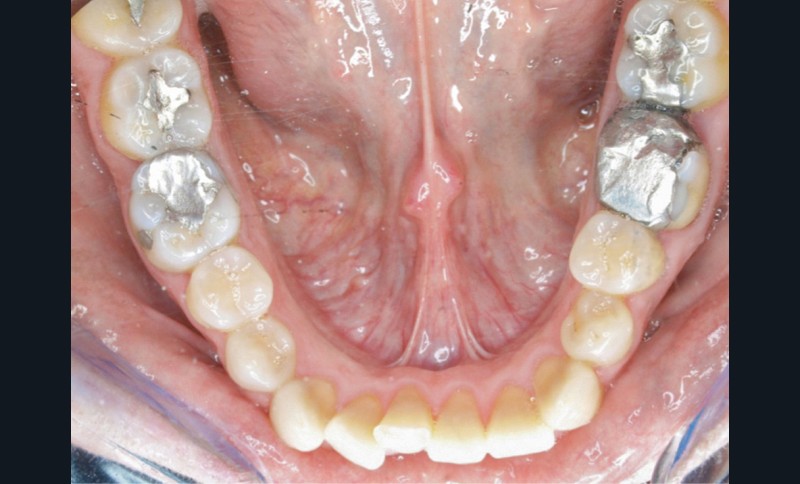

En 2008, la patiente, âgée de 34 ans, se présente pour le traitement de ses « dents mal placées, et de l’écart entre les dents du haut et du bas » (fig. 1). Elle a déjà bénéficié d’un traitement adolescent par plaque amovible maxillaire.

L’analyse endobuccale et l’étude céphalométrique (fig. 2, tableau 1) confirment le diagnostic de classe II squelettique hyperdivergente avec une classe II molaire et canine bilatérale, associée à un encombrement, à une dysharmonie du sens transversal par endoalvéolie maxillaire, et une béance antérieure par infra-alvéolie incisive maxillaire dans un contexte dysfonctionnel de la musculature péri-labiale et mentonnière.